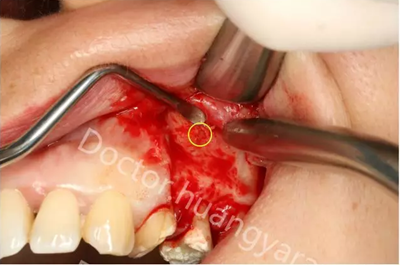

拍攝根尖片檢查,24、25牙根充到位,但考慮到可能是治療過程中消毒不到位導(dǎo)致,所以重新對25牙做根管治療,但酸痛感無減輕,于是考慮到根尖骨穿孔的可能性,與患者溝通后做診斷性翻瓣,翻瓣后發(fā)現(xiàn)根尖處無頰側(cè)骨板直接暴露,當(dāng)即行根尖切除術(shù),對位縫合,經(jīng)兩個月恢復(fù)根尖已無酸痛感!